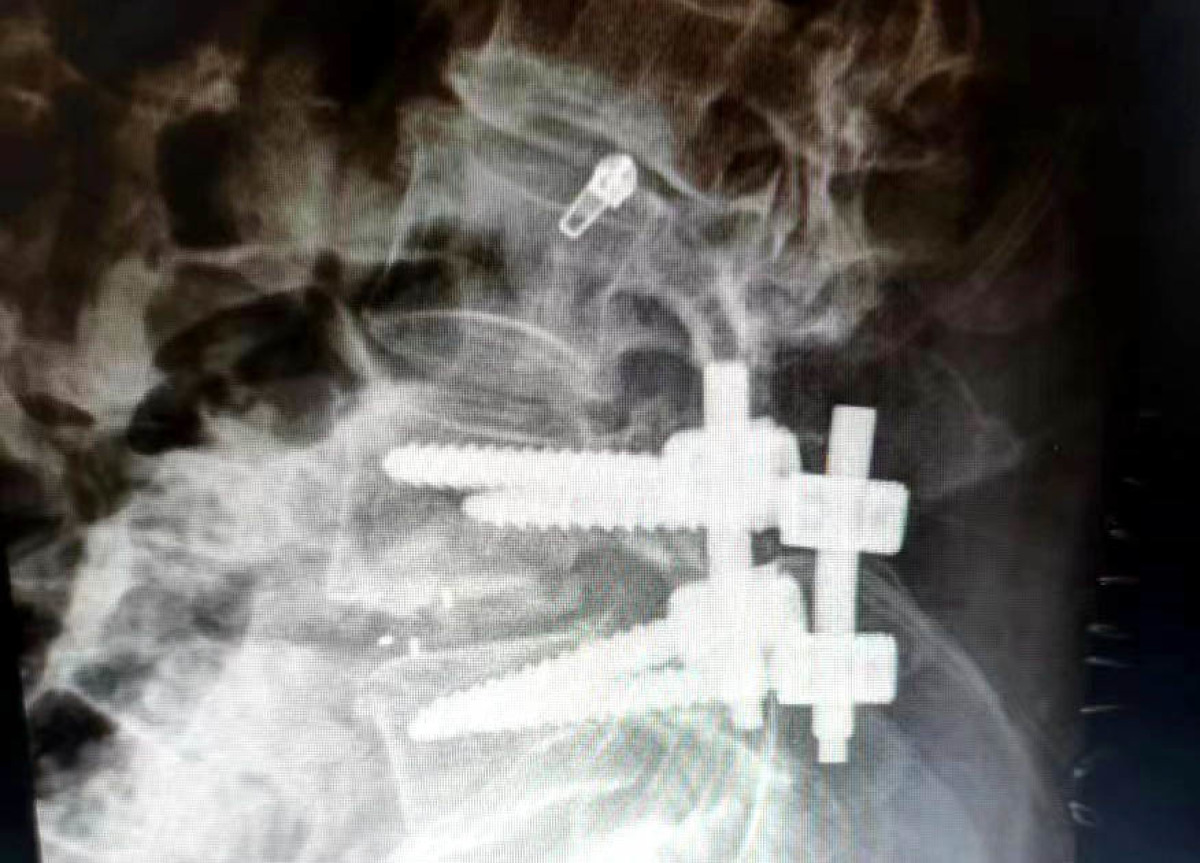

神经外科副主任刘沛涛接诊后,经过详细辅助检查,诊断为L5神经根病、腰椎滑脱、腰椎间盘突出症,需手术治疗。考虑到患者年龄大、体质差,传统手术方式切口大,术后卧床时间长,显微镜下微创手术操作更精细,治疗更精准,对患者机体损伤小,是目前治疗脊柱脊髓疾病的首选方案,但微创手术对手术适应症及手术技术的要求更高,因此科主任乔景尊组织科室团队反复讨论手术方案,进行充分术前评估后,刘沛涛及科室团队在麻醉科通力合作下,采取显微镜下L5神经根减压+腰间盘切除+椎间植骨融合+钉棒内固术,经过2个多小时的谨慎、精细操作,顺利完成了手术,患者安全返回病房。

术后第三天,患者在支具辅助下可以自行下床活动。刘大爷感激的说:“之前被病痛折磨多年,简直痛不欲生,现在腰也不疼了,俩腿也管走路了,感谢二院神经外科,感谢刘主任,手术做的真好!”